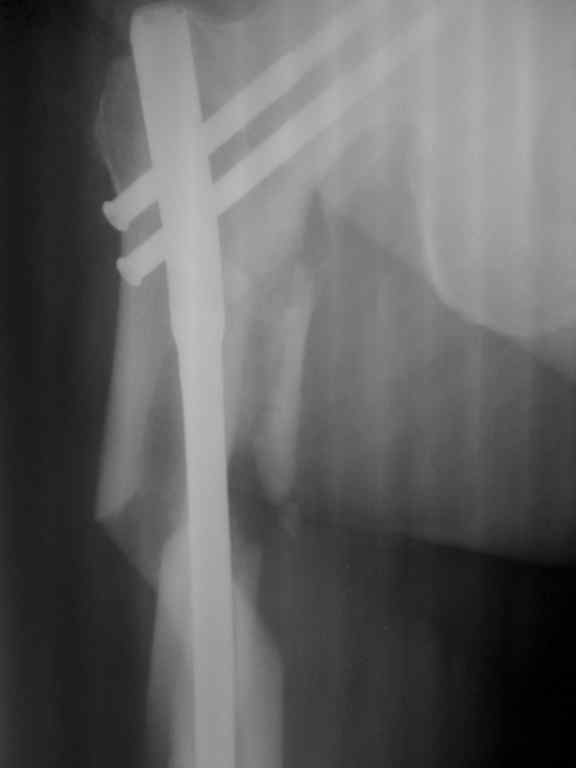

Сергей Дукер 28 Июнь 2010, 10:30

Р-гр после операции